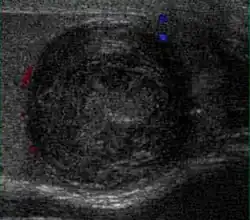

Fig. 10. Epidermoid cyst. Onion peel appearances of the tumor together with absence of vascular flow are typical findings of epidermoid cyst.

Epidermoid cysts, also known as keratocysts, are benign epithelial tumors which usually occur in the second to fourth decades and accounts for only 1–2% of all intratesticular tumors. As these tumors have a benign biological behavior and with no malignant potential, preoperative recognition of this tumor is important as this will lead to testicle preserving surgery (enucleation) rather than unnecessary orchiectomy. Clinically, epidermoid cyst cannot be differentiated from other testicular tumors, typically presenting as a non-tender, palpable, solitary intratesticular mass. Tumor markers such as serum beta-human chorionic gonadotropin and alpha-feto protein are negative. The ultrasound patterns of epidermoid cysts are variable and include:

However, these patterns, except the latter one, may be considered as non-specific as heterogeneous echotexture and shadowing calcification can also be detected in malignant testicular tumors. The onion peel pattern of epidermoid cyst [Fig. 10] correlates well with the pathologic finding of multiple layers of keratin debris produced by the lining of the epidermoid cyst. This sonographic appearance should be considered characteristic of an epidermoid cyst and corresponds to the natural evolution of the cyst. Absence of vascular flow is another important feature that is helpful in differentiation of epidermoid cyst from other solid intratesticular lesions.